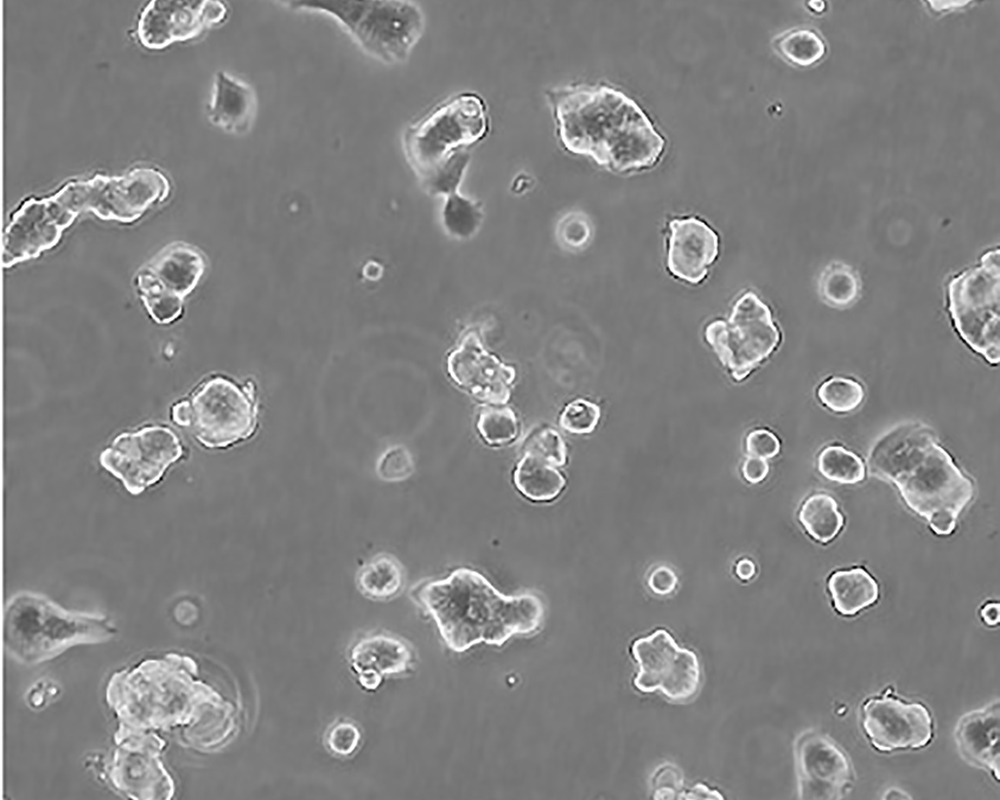

生長(zhǎng)特性 adherent

形態(tài)特征 epithelial

細(xì)胞描述 該細(xì)胞產(chǎn)生高水平的黏液素MUC-1 mRNA,低水平的MUC-2 mRNA,但不表達(dá)MUC-3基因;表達(dá)雌激素受體。